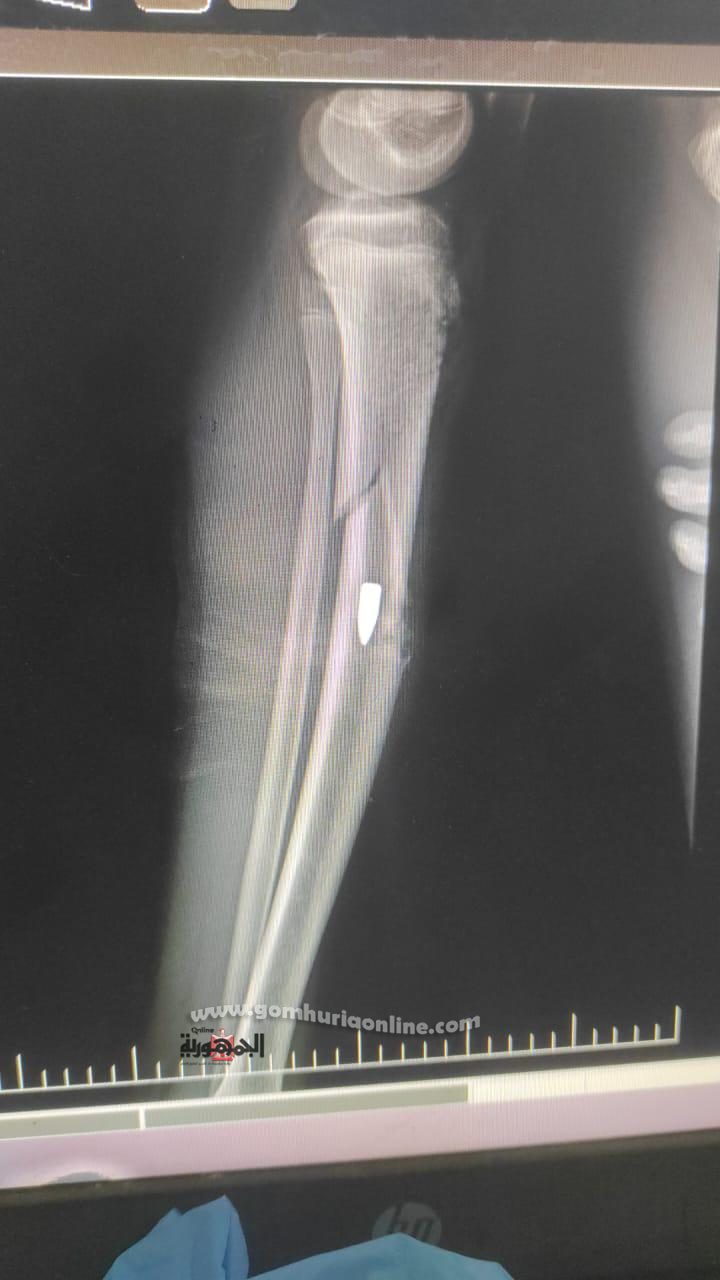

وكان المصاب وصل إلى استقبال قسم العظام في تمام الساعة 9:35 صباحًا من يوم الجمعة الموافق 6 يونيو 2025، وتم التعامل معه وفق البروتوكولات الطبية، حيث أُجريت له الفحوصات والإشعاعات اللازمة، وتبين وجود طلق ناري مستقر داخل تجويف العظم دون فتحة خروج، بالإضافة إلى كسر مفتوح، مع عدم وجود تهتك في الأعصاب أو الأوعية الدموية، وهو ما ساعد في الحفاظ على سلامة الطرف المصاب.

تم تقديم الإسعافات الأولية وتثبيت الكسر مؤقتًا بجبيرة، ثم نُقل المصاب إلى القسم الداخلي للعظام، حيث تلقى الرعاية الطبية والمتابعة لحين تجهيزه للعملية، مع إجراء الغيارات اليومية على الجرح لضمان نظافته حتى لا يؤثر على إجراء العملية، وبعد استكمال الفحوصات، أُدرج على جدول العمليات، وخضع لجراحة دقيقة شملت استخراج الطلق، وتنظيف موضع الإصابة، ورد الكسر، وتثبيته باستخدام مثبت خارجي.

وأوضح الدكتور محمد الديب، مدير مستشفى قنا العام، بأن الحالة كانت معقدة وتستلزم تدخلًا دقيقًا ، مشددًا على أن الجراحة تمت بنجاح كامل، وأن المصاب الآن في حالة مستقرة، ويتلقى الرعاية الطبية اللازمة، وسيتم خروجه بعد التنسيق مع الجهات الأمنية.